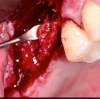

A re-entry to the maxillary sinus was performed. Once the sinus tract was excised, it was visibly evident that the bone graft had been invaded by granulation tissue. The graft was then removed and sent for histopathological evaluation (Figure 6). Intraoperatively, no perforation, defect, or communication to the maxillary sinus was detected; even a distinct layer of solidified grafting material covered the Schneiderian membrane (Figure 7). The histopathological examination reported an acute and chronic inflammation of bone consistent with avascular bone grafting material. Different sections revealed a well-vascularized fibrous connective tissue containing viable and nonviable bone trabeculae and an inflammatory infiltrate of lymphocytes and plasma cells. Focally, the presence of aggregate of necrotic debris, fibrin, and white blood cells was observed (Figure 8).

Fig 6. Intraoperative photograph showing re-entry to the maxillary sinus and removal of the non-consolidated bone graft material.

Figure 6